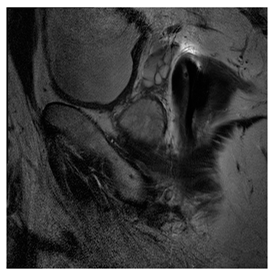

Breast-MRI-NACT-Pilot is an MRI-type image database, collecting breast medical images of 64 patients. Some samples are shown in Figure 12a.

Figure 12.

Sampled images in the tested benchmark databases: (a) Breast-MRI-NACT-Pilot (breast), (b) ACRIN-DSC-MR-Brain (brain), (c) NIH (chest), (d) Lung-PET-CT-Dx (lung), (e) Prostate-MRI (prostate), and (f) Other grayscale standard images.